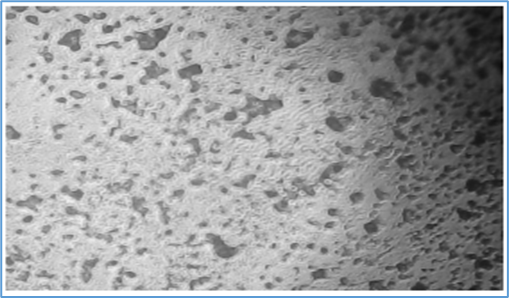

In-vitro scratch assay

Percentage (%) of cells that moved in the direction of the wound and helped it close microscopically images representing the In vitro wound healing nature of Sample: L929 cells were incubated in presence or absence of Samples and standard drug Cipladine and images were captured at 48 hours. According to images and results Sample showed Moderate activity Percentage (%) of cells that moved in the direction of the wound and helped it close.

Figure 2: Normal Morphology of L929

Control - Wound Scratch                                       After 48 hours - Control

Standard - Wound Scratch (Cipladine)                 After 48 hours - Standard (Cipladine)

Sample - Wound Scratch                                 After 48 hours - Sample

Table 2 Percentage (%) of Cells Reduction in Wound Closure.